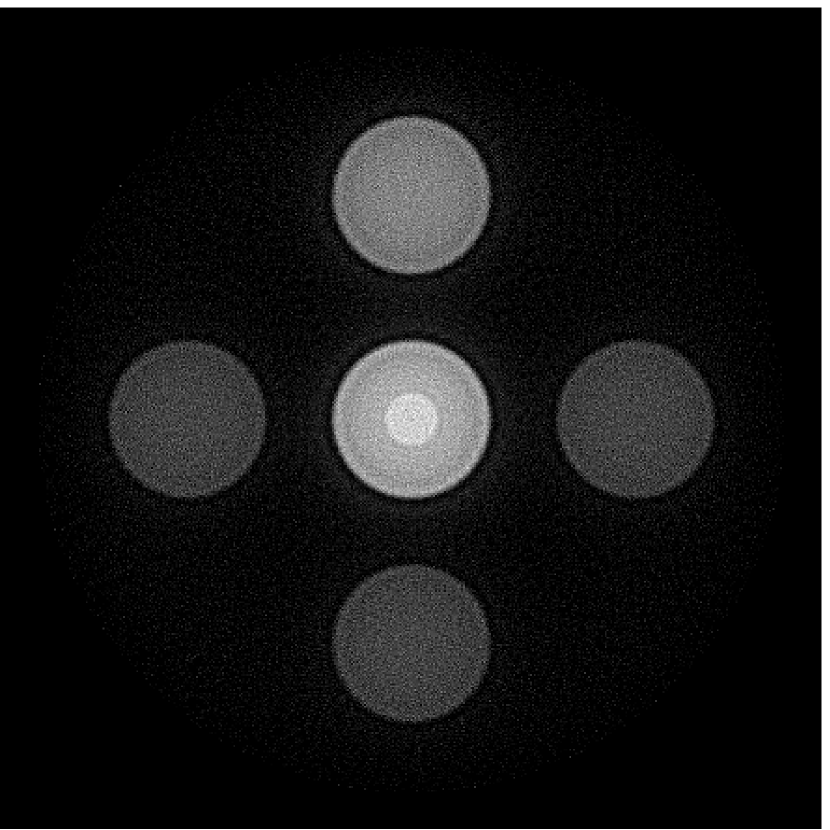

Figure 2(a) shows the image reconstructed by use of the conventional iterative method that utilized a system matrix based on EIR-2. Different values of the regularization parameter from the interval were considered. The reconstructed image with the value of that minimized the RMSE was chosen to represent the best performance of the conventional iterative method. Figure 2(a) and the profile in Figure 2(c) demonstrate that the use of an inaccurate EIR can result in strong artifacts and distortions in images reconstructed by use of the conventional methods.

When the VP algorithm was applied, different values of the regularization parameter from the interval and from the interval were considered. The image that minimized the RMSE was chosen and displayed in Figure 2(b). As revealed by this image and the profiles in 2(c), the VP algorithm yielded an image with fewer artifacts and distortions, and image fidelity was improved as reflected by the reduced RMSE.